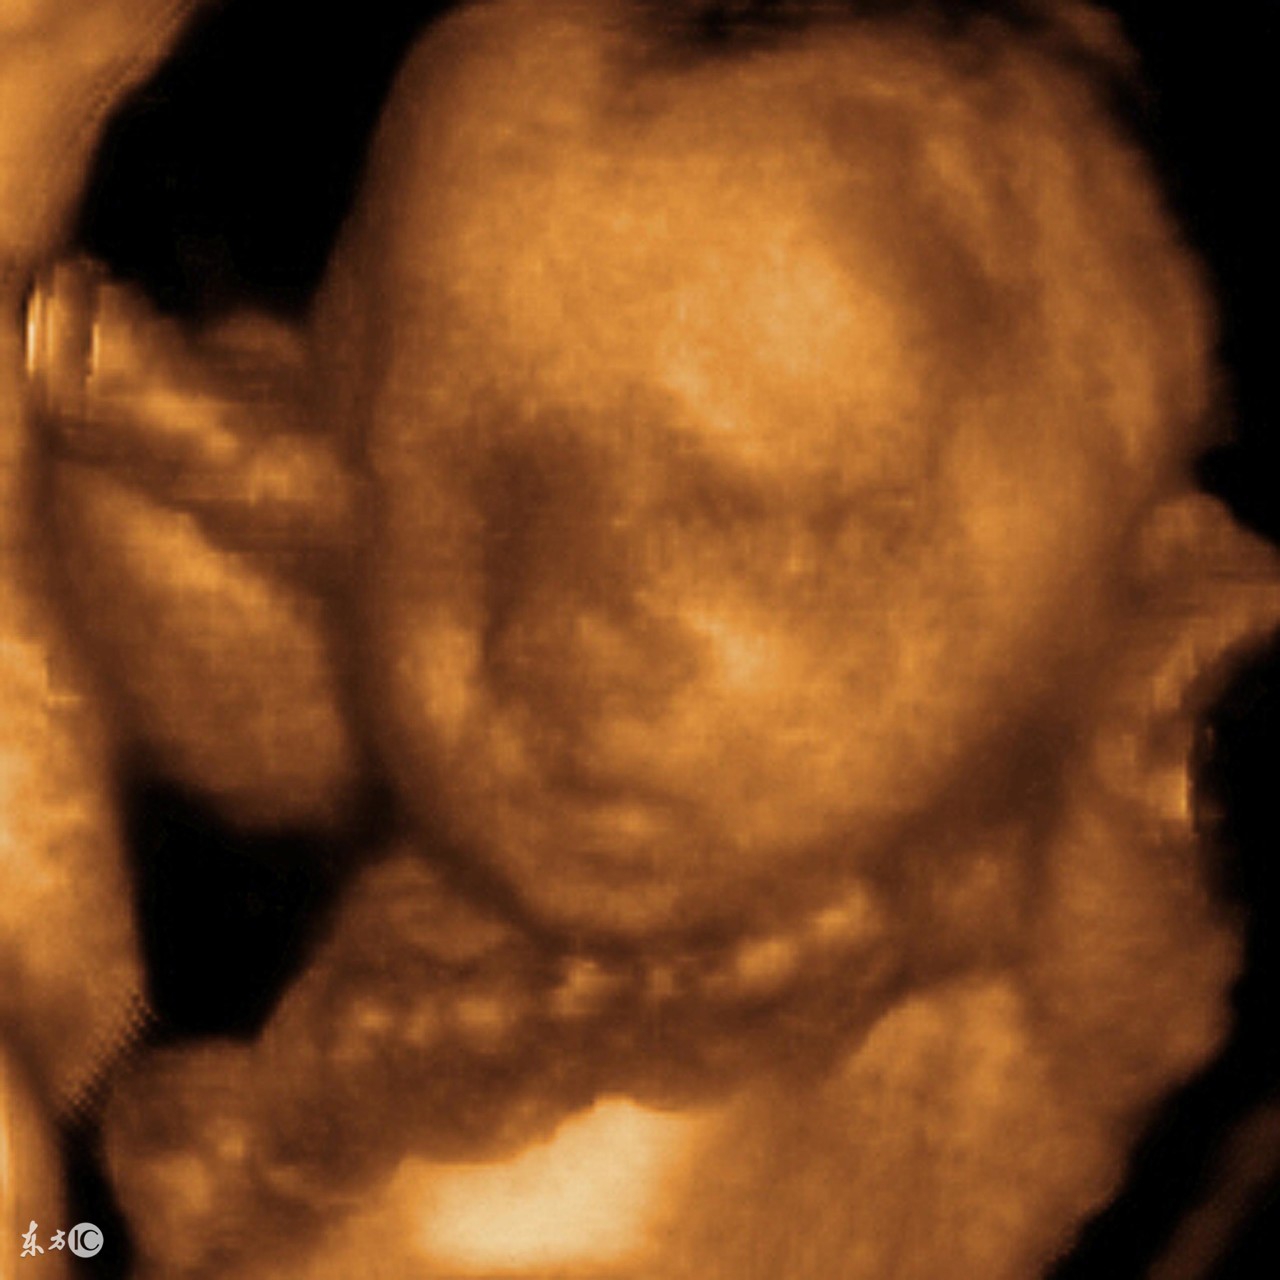

孕育宝宝是一件神奇的事情,但期间总会遇到种种险情,其中最常见的是胎儿脐带绕颈。当脐带绕颈过于严重,将会影响胎儿的氧气供应。不过现代医学B超可以看到胎宝宝绕颈情况,为此也降低了一定的风险。脐带绕颈发生率很高,几乎可以达到50%,不过并不是所有脐带绕颈都很危险。只要在安全范围控制以内,对宝宝的影响是不大的。

那为什么超声可以看到脐带绕颈呢?胎儿在宫内可以绕手,可以绕脚,可以绕身,为什么容易看到颈部绕脐呢?其原因在于颈部较细,容易看,容易判断。说到这里,舟舟妈妈不得不提一下,舟舟妈妈在怀舟舟34周的时候,也被告知脐带绕颈,绕颈一周。舟舟妈妈咨询产科医生,医生说如果保持现状,没有更严重的话,是不影响顺产的。